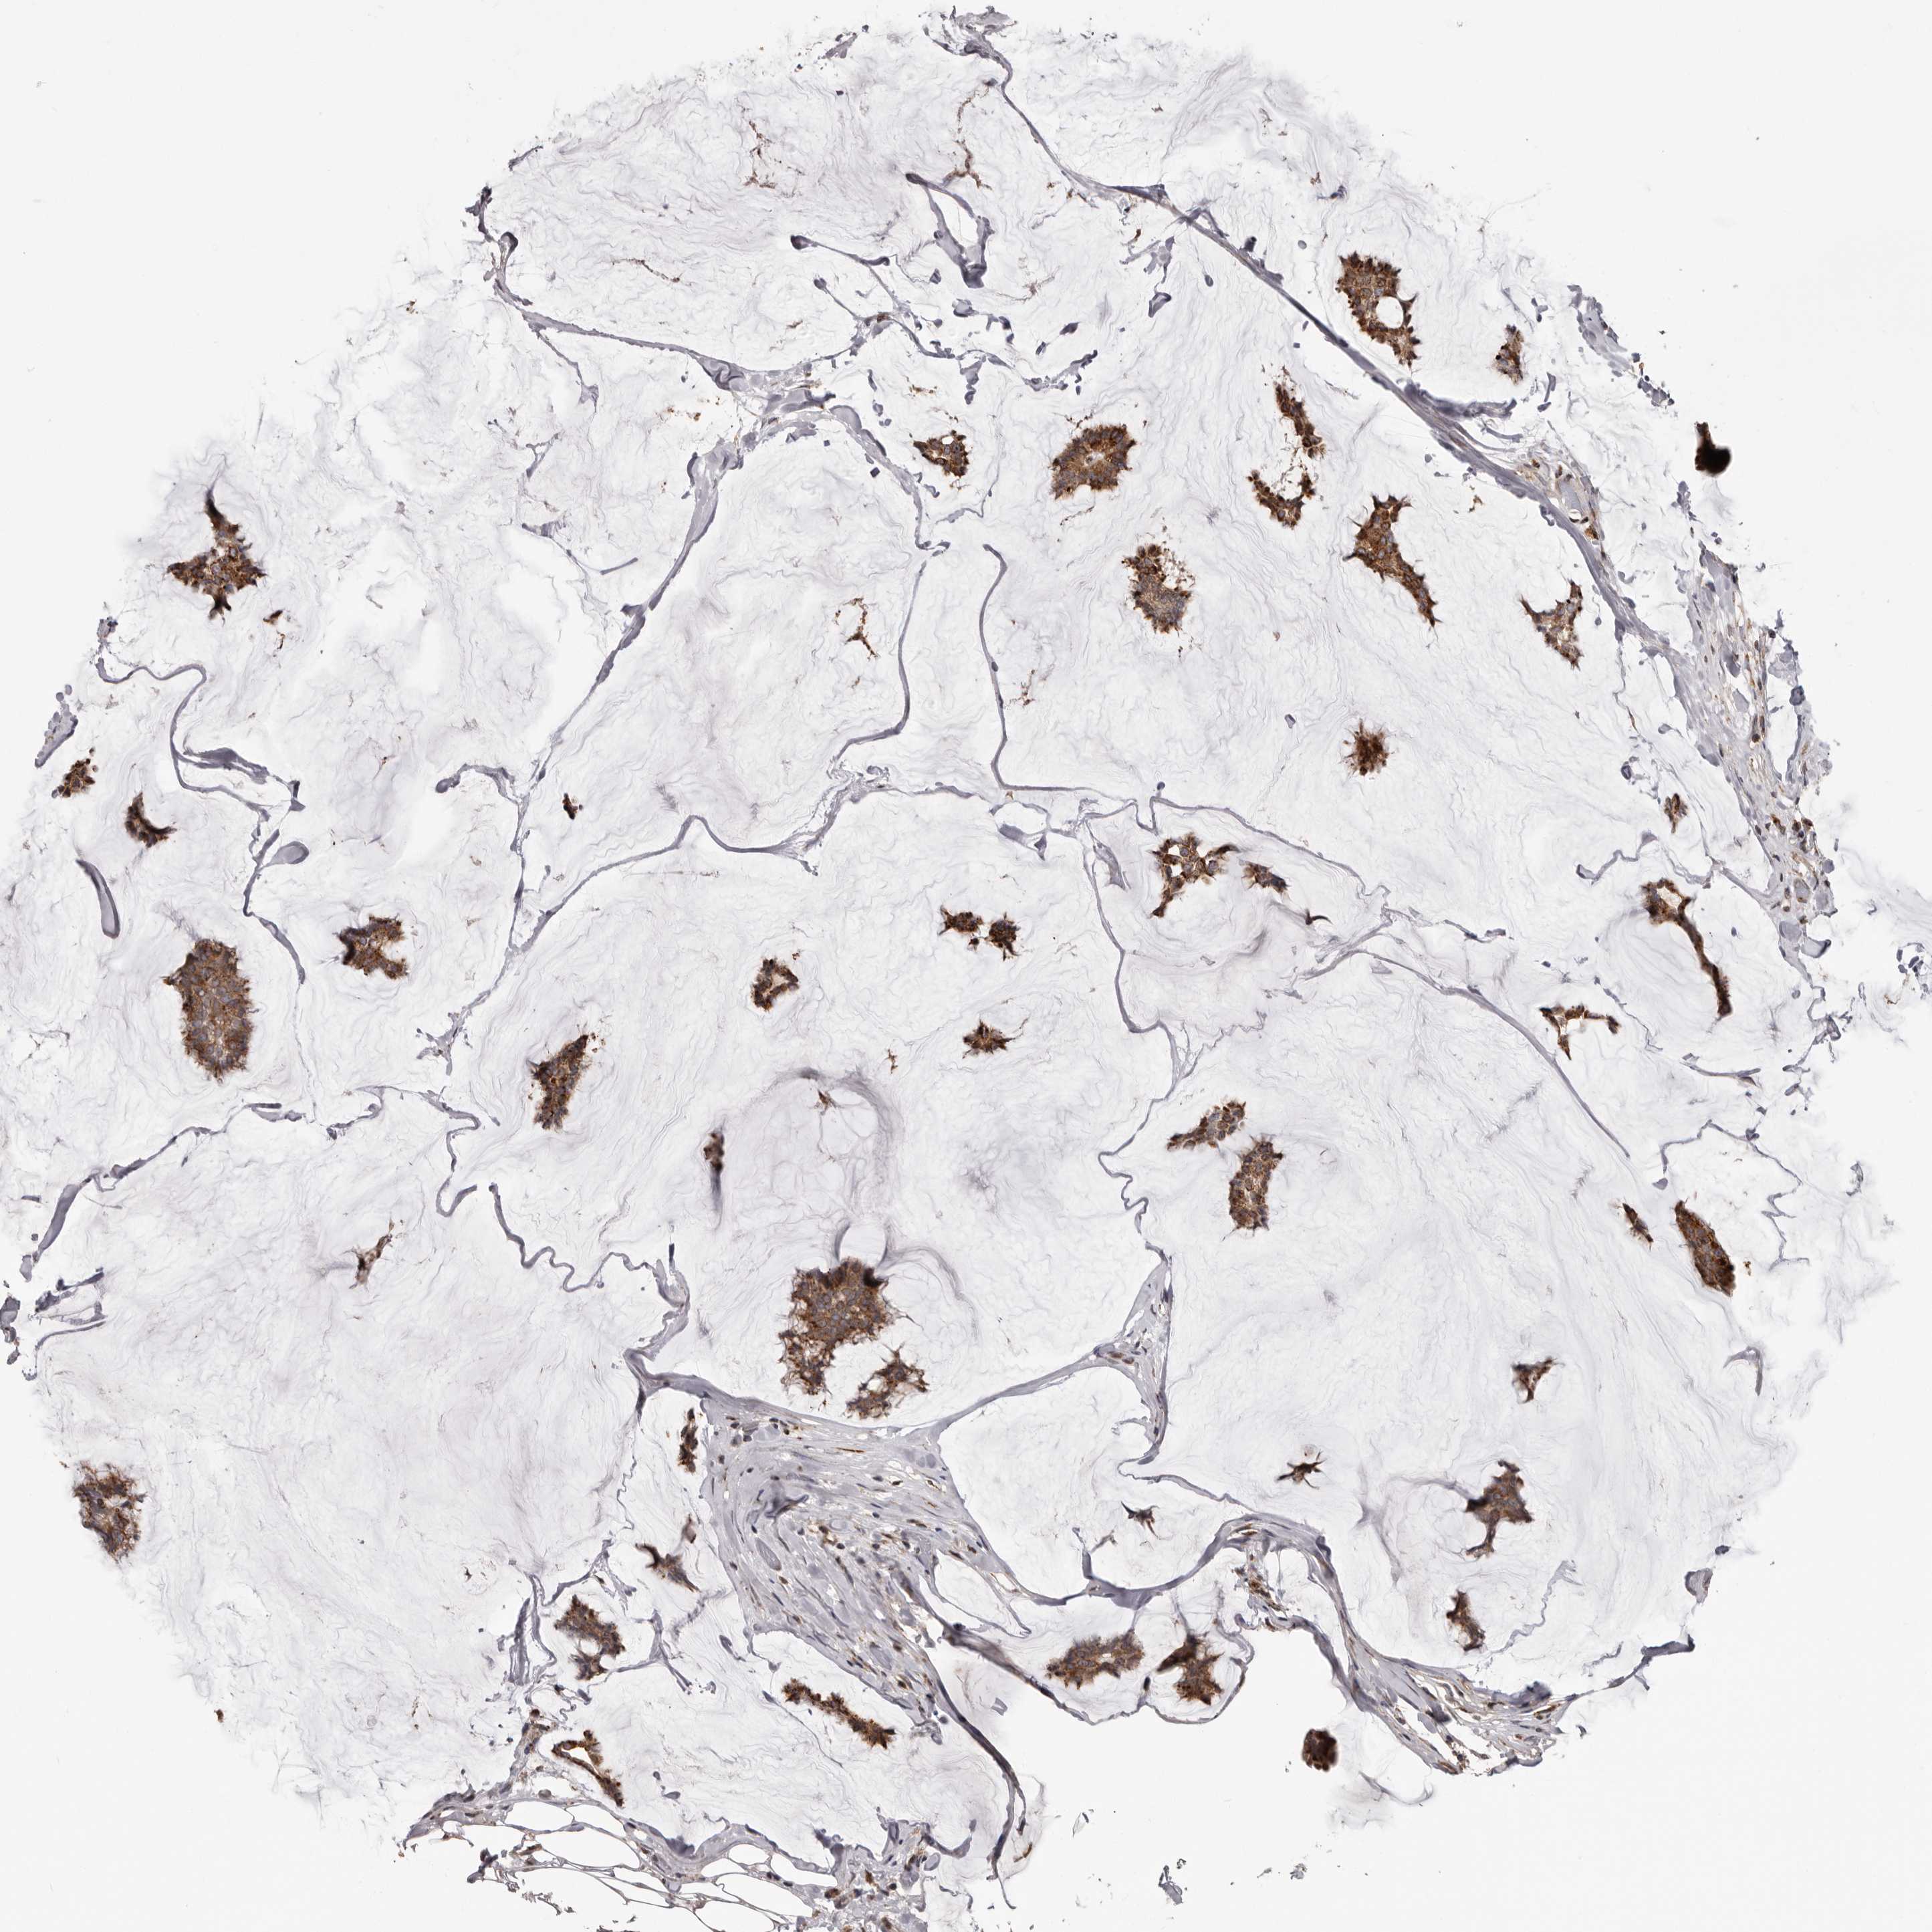

CANCER BREAST CANCER Show tissue menu

BRCA TCGA BRCA VALIDATION PROTEIN EXPRESSION